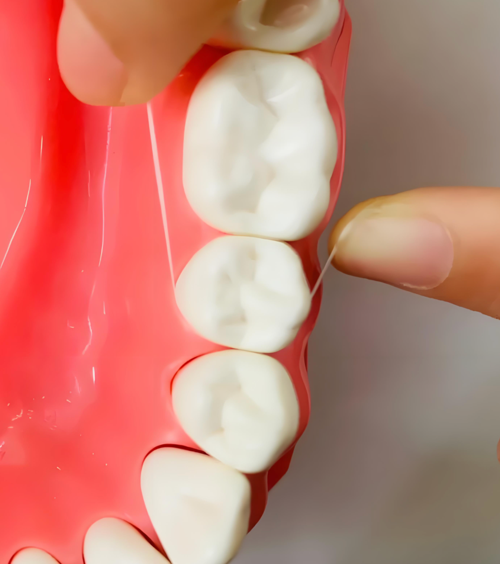

1. 牙线是唯一解药:必须每天至少使用一次牙线或牙线棒。正确方法是将牙线呈“C”字形包裹牙侧面,上下刮擦,而非粗暴地拉锯式来回拉动。这个动作能有效清除邻面的菌斑。

图2:展示牙线以“C”字形环绕牙齿侧面,清洁牙龈沟和邻面区域的示意图。